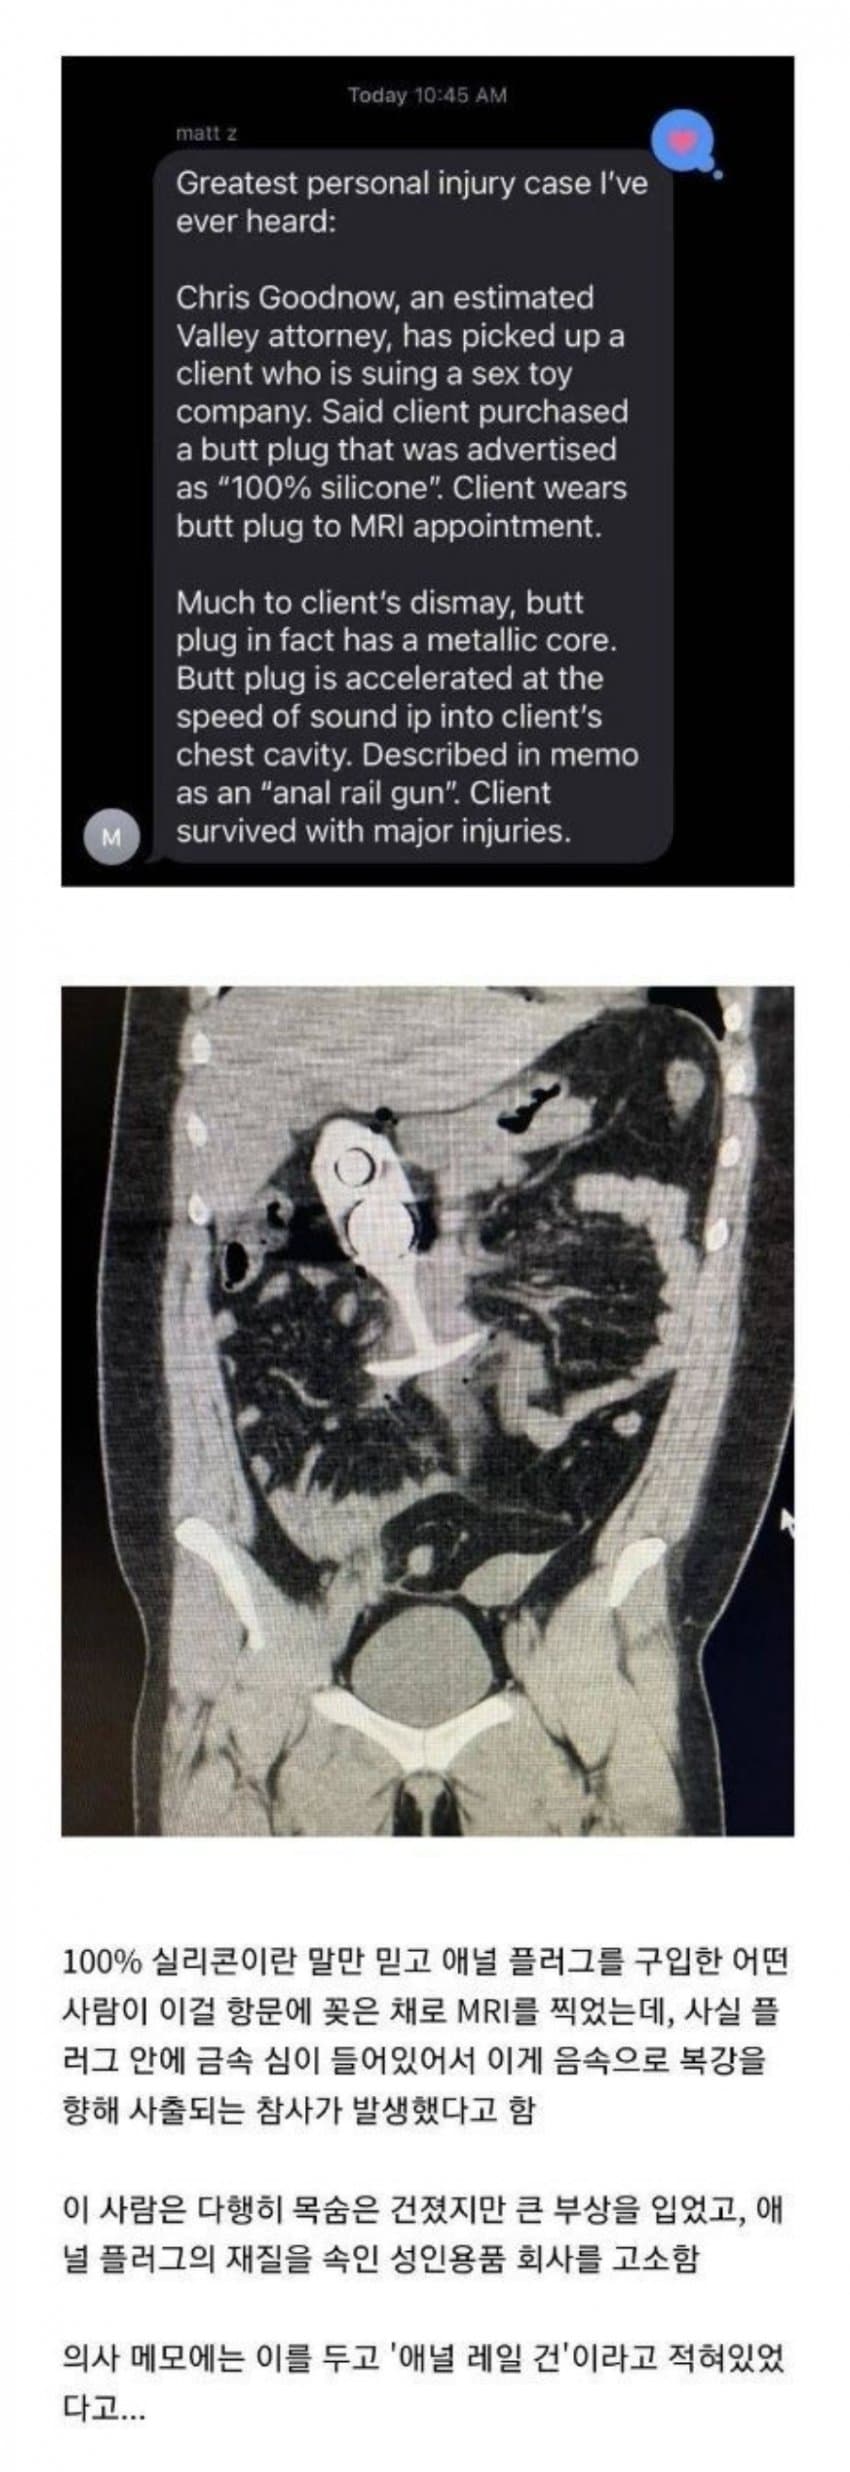

Àü¿¡º¼¶© ¸ô¶ú´Âµ¥ Áö±Ýº¸´Ï ¸ÞÅ» ¾ÆÆ¼ÆÑÆ®°¡ ³Ê¹« ÀûÀº°Ô ÇÕ¼º°°´Ù. Ç÷¯±× ÁÖÀ§·Î´Â ºû¹øÁüÀÌ ½ÉÇØ¼­ ¹¹°¡¹ºÁö ¸ð¸¦Á¤µµ¿©¾ßÇϴµ¥ °£ °æ°è¸é±îÁö ´Ù º¸ÀÌ³× [3]

¹æ»ç¼±»çÀÔ´Ï´Ù CT¿µ»ó¿¡ MAR(Metal Artifact Reduction) ±â¼ú Àû¿ë½Ã Àú·¸°Ô ¸ÞÅ» ¾ÆÆ¼ÆåÆ®¸¦ ÃÖ¼ÒÈ­½Ãų ¼ö ÀÖ½À´Ï´Ù